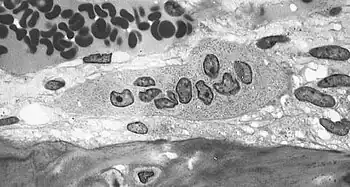

Osteoclasts are located on the surface of bones and form resorption pits by excreting H+ to the bone surface removing hydroxyapatite, multiple bone minerals, and organic components: collagen and dentin. The purpose of bone resorption is to release calcium to the blood stream for various life processes.[17] These resorption pits are visible under electron microscopy and distinctive trails are formed from prolonged resorption. Osteoclasts have shown to be "absolutely dependent on extracellular acidification".[14] A drop in pH of <0.1 units can cause a 100% increase in osteoclast cell activity, this effect persists with prolonged acidosis with no desensitization, "amplifying the effects of modest pH differences". Osteoclast cells show little or no activity at pH 7.4 and are most active at pH 6.8 but can be further stimulated by other factors such as parathyroid hormone.[16]